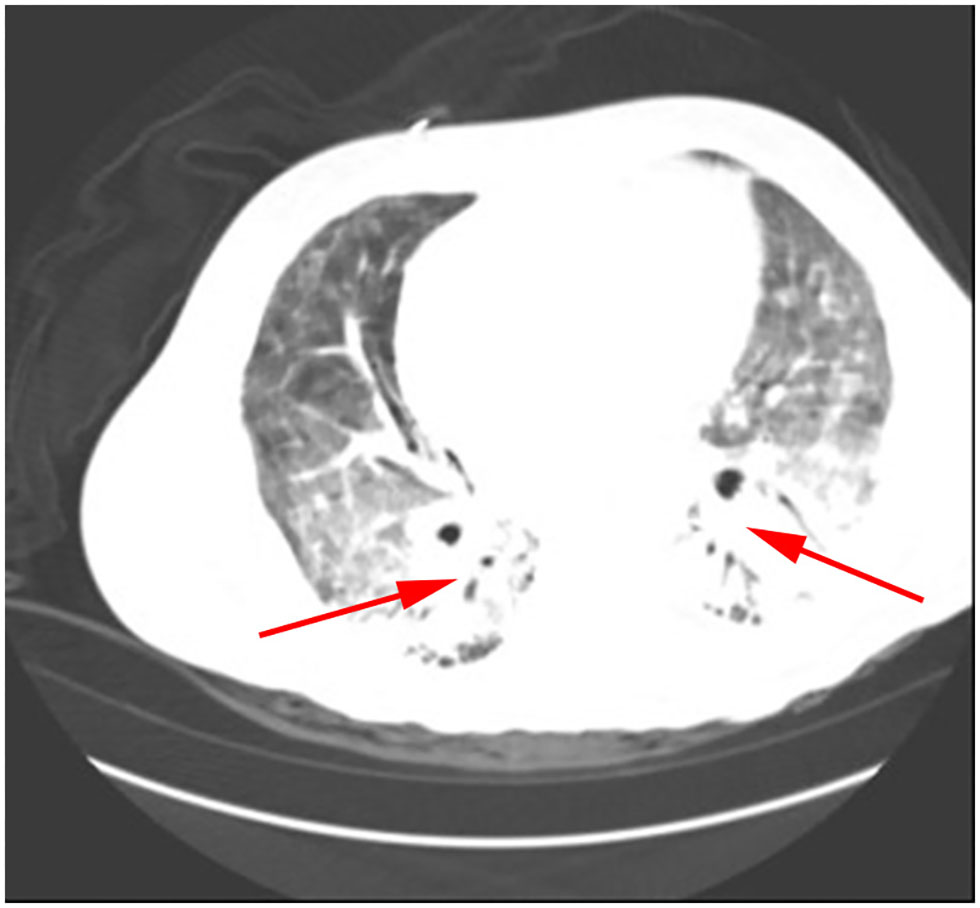

Klebsiella pneumoniae were detected by traditional microbiological testing. Chest CT showed large meshes in both lungs with multiple nodules (Figure 4). BALF was collected for examination on the seventh day of admission. GMS (Figure 2C) and mNGS all detected P. jirovecii, but the detection period of mNGS was 1 day shorter than that of GMS. mNGS results showed that sequence number of P. jirovecii was 34 (Table 2). Based on the GMS and mNGS results, the patient was diagnosed with PJP. At the beginning of treatment, the patient was treated with tigecycline, biapenem, penciclovir, voriconazole, methylprednisolone, and other symptomatic treatments. When the results of mNGS were showed, specific anti P. jirovecii drugs were given. Unfortunately, the progress of this patient was the same as that of the previous patients. Even upon mechanical ventilation, continuous renal replacement therapy (CRRT), and other rescue treatments, there was still no improvement. Ultimately, he gave up treatment and was automatically discharged on the eleventh day of admission.

Figure 4

P. jirovecii appearances on Chest CT scan in patient 3 as a large number of meshwork shadows and multiple small nodules in both lungs.

Patients with HIV who are also infected with P. jirovecii usually present with fever, dry cough, dyspnea, and ground-glass opacity (GGO) imaging on chest CT. According to our observations, the main manifestations of the patients were fever, chest tightness, and dyspnea. In addition, chest CT showed multiple patchy, flocculent, and grid-like high-density shadows. Due to its atypical early symptoms and radiographic findings, it is easy for it to be clinically ignored, which eventually leads to delayed disease recognition and treatment. Although our clinicians did empirically administer antifungals, the outcome of patients was not satisfactory. All four of the patients in this study rapidly deteriorated and were transferred to the ICU for severe respiratory failure, pulmonary infection, and mechanical ventilation. Therefore, we need to identify the etiology as soon as possible so as to make an early diagnosis and begin early treatment.